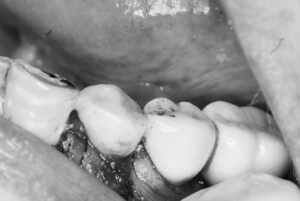

左下4番の抜歯と同時にインプラントの埋入オペをし、即時に仮歯を装着し噛めるようにする難易度の高いオペです。患者さんは2週間前にも右下に同様のオペをされた方です。

骨質を見極めたドリリングテクニックはいつもの様にスムーズに行われ骨との合着値も良い結果が出ています。